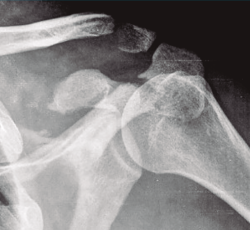

Figura 3. Radiografía simple de fractura glenoidea.

Existen distintos tipos de fracturas escapulares. En ocasiones, tras una fractura glenoidea (35%) (Figura 3), pueden producirse fracturas de coracoides (7%) (Figura 4) y también pueden ocurrir fracturas escapulares indirectas por caídas con la mano extendida(1,3,5).